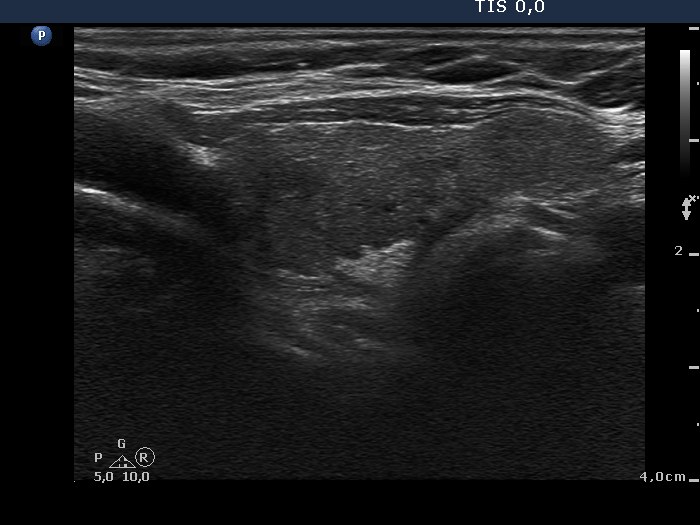

Follicular adenoma - Case 5. |

Clinical data: a 67-year-old woman was referred for an evaluation of a nodule discovered on carotid Doppler examination.

Palpation: a firm nodule in the right lobe.

Ultrasonography: the thyroids were minimally-moderately hypoechogenic. There was a moderately hypoechogenic nodule in the right lobe. The nodule displayed a halo sign and perinodular blood flow.

Cytological diagnosis: follicular tumor. Lymphocytic thyroiditis.

Histopathological diagnosis: microfollicular adenoma. Chronic lymphocytic thyroiditis.